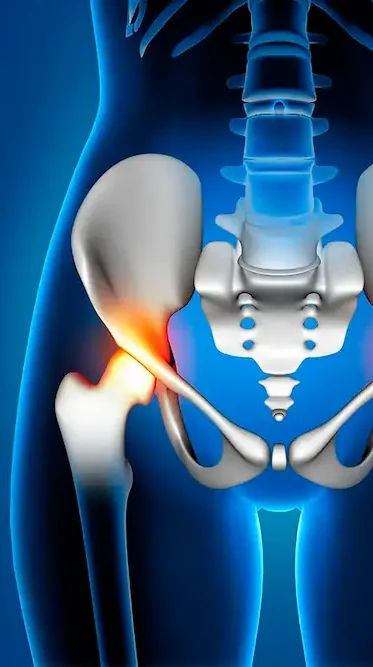

O impacto femoroacetabular acontece quando há uma deformidade na cabeça do fêmur (impacto tipo Cam) ou no acetábulo (impacto tipo Pincer), ou em ambos, que causa atrito entre os ossos durante os movimentos do quadril. Este atrito pode danificar a cartilagem articular e o labrum, que são estruturas importantes para a mobilidade e a estabilidade do quadril.

- Tipo Cam: Ocorre quando a cabeça do fêmur tem uma forma irregular e não se encaixa perfeitamente na cavidade do acetábulo. Isso leva a um desgaste da cartilagem ao redor do acetábulo.

- Tipo Pincer: Ocorre quando o acetábulo cobre excessivamente a cabeça do fêmur, resultando em um contato anormal entre os ossos.

- Misto: É a combinação das duas deformidades, onde há características de ambos os tipos Cam e Pincer.